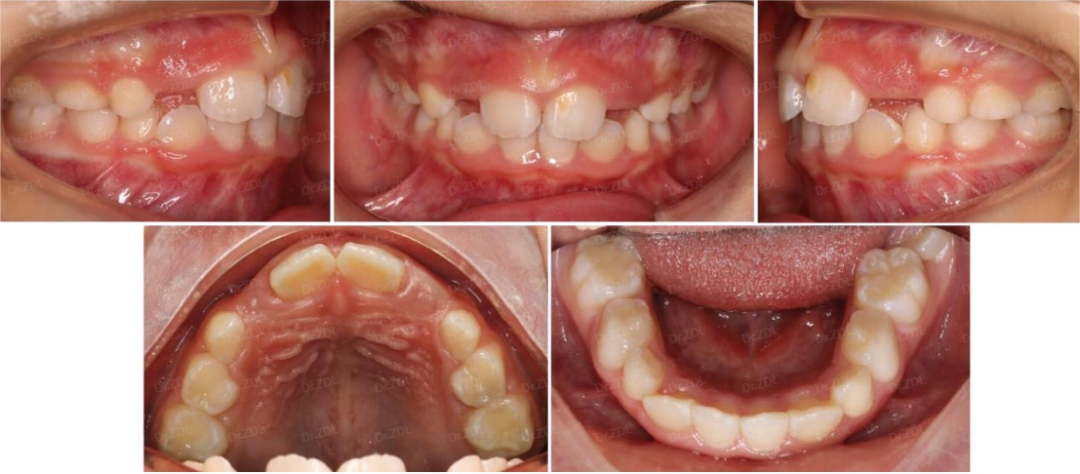

Grace硅胶牙套案例2:

这位6岁小朋友,主诉牙凸,临床检查看上前牙III度深覆合深覆盖,上颌牙弓狭窄,牙齿存在散在间隙。

早期矫正方案利用好孩子替牙期的生长发育潜力,结合孩子的牙齿情况和面型情况,制作Grace个性化定制硅胶牙套佩戴。

佩戴 Grace12 个月,上下颌牙弓形态恢复正常,牙齿排齐良好,上前牙角度恢复良好,前牙咬合打开良好,前牙正常覆合覆盖。